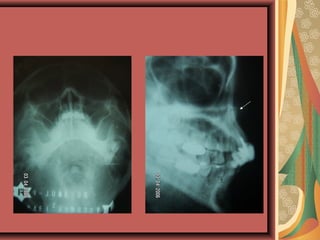

for lower 8s-Oblique lateral view of L + R side of

mandible

for upper 8s- Occipito mental 0· / 10· / 15· / 30· ,

True lateral